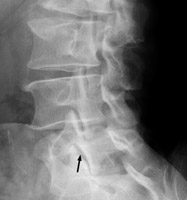

On the oblique view of the lumbar spine, the outline of a dog can seen. The parts of the dog are as follows: the transverse process-the nose; the pedicle-the eye; the pars interarticularis-the neck; the superior articular facet-the ear; the inferior articular facet-the front leg. A break in the neck of the dog, or a dog collar, corresponds to a fracture in the region of the pars interarticularis, which is specific for spondylolysis. It is important to recognize as it is a cause of low back pain. A. Normal. B. L5 Pars defect.

Oblique lumbar spine - Click on the image for a larger versionAOblique lumbar spine - Click on the image for a larger versionB